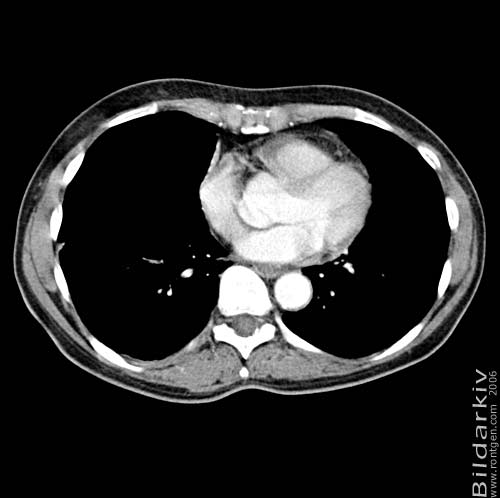

Snitt över thorax med kontrast. Sk. mediastinum-fönstersättning.

Mediastinum